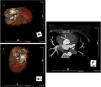

She underwent coronary angiography (CA) during which selective cannulation of the left coronary artery (LCA) was not possible, and a non-selective injection disclosed no coronary artery arising from the left coronary sinus. On selective injection of the right coronary sinus, a single ostium was visualized. The right coronary artery (RCA) was a great vessel, with no stenosis. A hypoplastic left anterior descending artery (LAD) and left circumflex artery (LCx) were perfused from RCA collateral vessels, both without lesions (Figure 2). Left ventriculography revealed apical ballooning akinesis, basal hyperkinesis and severe LV dysfunction (Figure 3).

Coronary angiography in multiple projections disclosing no coronary artery arising from the left coronary sinus (a); a single coronary artery originating from the right ostium – a large caliber right coronary artery – with no lesions (b); antegrade flow through a posterior lateral branch to the left circumflex artery (LCx) and to the hypoplastic left anterior descending artery (LAD) (b-d); the posterior descending artery gives off collaterals to the distal segment of the LAD (c). Both LCx and LAD had no lesions (c, d).